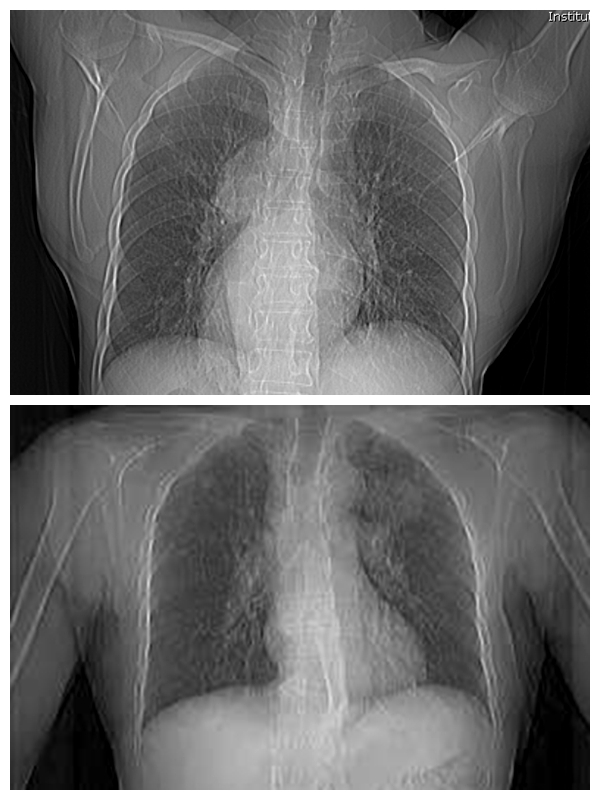

镜面人(上)与正常人(下)胸片对比图

家人带黄大爷来到湘雅常德医院就诊,心胸外科黄日茂主任一拿到胸部CT检查的结果初步一看,还以为拿反了。因为影像上显示,黄大爷所有器官的左右位置都与正常人的相反。仔细一看,原来黄大爷是罕见的“镜面人”。详细检查后发现,该患者不但存在内脏反位,而且肺部发现一肿物,需行外科手术治疗。

“黄大爷所有器官的功能都正常,但位置却是反的。”黄日茂主任介绍,黄大爷的心、肝、胰、脾、肺、胆等内脏的位置全部颠倒,医学界称为“全内脏转位”,俗称“镜面人”。因为黄大爷是“镜面人”在手术操作过程中,医生需要利用逆向思维,将常规的右侧解剖变成左侧解剖,这大大增加了手术难度。

据悉,“镜面人”又称“镜子人”或“镜像人”,即心、肝、脾、胆等内脏器官的位置与正常人相反,所有的内脏器官如同正常人在镜子中的影像一样。由于只是内脏器官位置发生变化,内脏之间的相互关系并未改变,“镜面人”的生理功能与正常人一样,对身体健康、生活都没有影响。